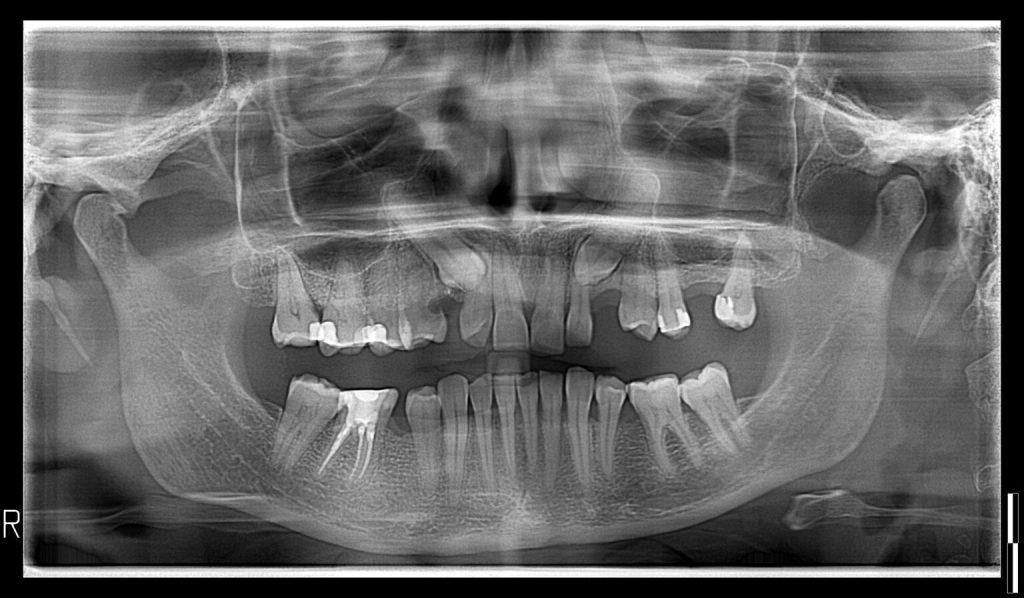

Calidad de imagen excepcional